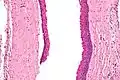

| Micrograph of an odontogenic keratocyst. H&E stain. | |

Histology

Odontogenic keratocysts have a diagnostic histological appearance. Under the microscope, OKCs vaguely resemble keratinized squamous epithelium;[14] however, they lack rete ridges and often have an artifactual separation from their basement membrane.[2]

The fibrous wall of the cyst is usually thin and uninflamed. The epithelial lining is thin with even thickness and parakeratinised with columnar cells in the basal layer which have focal reverse polarisation (nuclei are on the opposite pole of the cell).[12] The basal cells are an indication of the odontogenic origin as they resemble pre-ameloblasts. The epithelium can separate from the wall, resulting in islands of epithelium. These can go on to form 'satellite' or 'daughter' cysts, leading to an overall multilocular cyst.[9] Presence of daughter cysts is particularly seen in those with NBCCS.[12] Inflamed cysts show hyperplastic epithelium which is no longer characteristic of OKCs and can have resemblance to radicular cysts instead. Due to areas of focal inflammation, a larger biopsy is required for correct diagnosis of odontogenic keratocysts.[9]